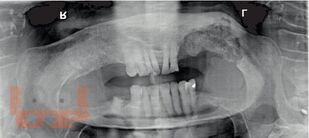

Остеонекроз челюсти

Журавлев А. Н. Остеонекроз челюсти : Учебно-методическое пособие для ординаторов специальностей 31.08.74 Стоматология хирургическая, 31.08.69 Челюстно-лицевая хирургия / А. Н. Журавлев, Л. Б. Филимонова, А. А. Кабанова. - Рязань : РязГМУ, 2024. - 56 c. - Текст : электронный // ЭБС "Букап" : [сайт]. - URL : https://www.books-up.ru/ru/book/osteonekroz-chelyusti-17719937/ (дата обращения: 16.03.2026). - Режим доступа : по подписке.

Настоящее учебно-методическое пособие составлено в соответствии с программой ФГОС ВО, предназначено для ординаторов специальностей 31.08.74 Стоматология хирургическая и 31.08.69 Челюстно-лицевая хирургия.